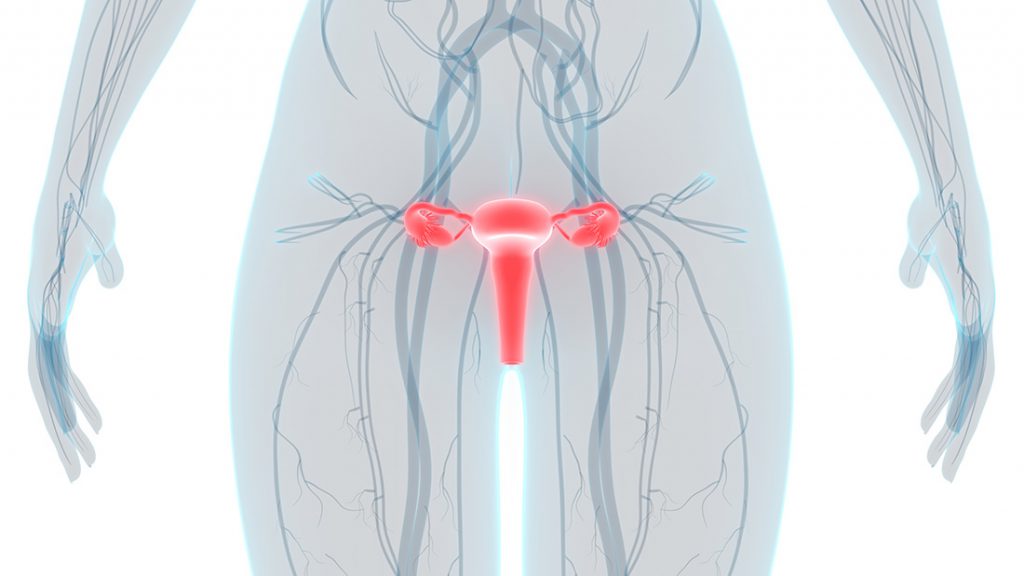

Female Genito-Urinary Cancers

When cancer starts in a woman's reproductive organs, it is called gynecologic cancer. The five main types of gynecologic cancer are: cervical, ovarian, uterine, vaginal, and vulvar.

Gynecological cancer

Gynecologic cancer is any cancer that starts in a woman’s reproductive organs. Cancer is always named for the part of the body where it starts. Gynecologic cancers begin in different places within a woman’s pelvis, which is the area below the stomach and in between the hip bones.

Each gynecologic cancer is unique, with different signs and symptoms, different risk factors (things that may increase your chance of getting a disease), and different prevention strategies.